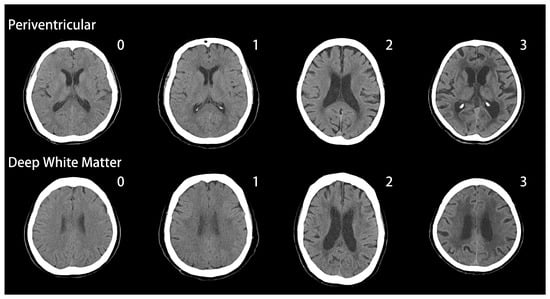

2.2. Evaluation of White Matter Changes

- Wahlund, L.; Barkhof, F.; Fazekas, F.; Bronge, L.; Augustin, M.; Sjögren, M.; Wallin, A.; Ader, H.; Leys, D.; Pantoni, L. A new rating scale for age-related white matter changes applicable to mri and ct. Stroke 2001, 32, 1318–1322. [Google Scholar] [CrossRef] [PubMed]

- Wahlund, L.-O.; Westman, E.; van Westen, D.; Wallin, A.; Shams, S.; Cavallin, L.; Larsson, E.-M. Imaging biomarkers of dementia: Recommended visual rating scales with teaching cases. Insights Imaging 2017, 8, 79–90. [Google Scholar] [CrossRef] [PubMed]